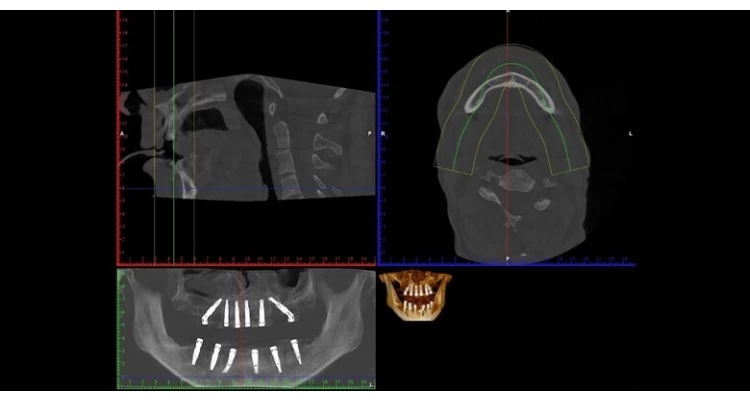

CBCT 3D snimka kompletne gornje i donje čeljusti uz detaljnu analizu snimke, besplatan dentalni pregled i konzultacije - uklonite sumnje na određene bolesti usne šupljine

Napredna CBCT 3D dijagnostika za najzahtjevnije zahvate

U korak s vrhunskim dentalnim standardima u Dentalno implantološko protetskom centru Hurčak dostupan je najsuvremeniji CBCT uređaj – Planmeca Viso™ G3. Ova napredna tehnologija omogućuje visokoprecizno 3D snimanje zubi, čeljusti i jagodičnih (zigomatičnih) kostiju, čime otvaramo novo poglavlje u dijagnostici i planiranju složenih zahvata.

Zahvaljujući vrhunskoj 3D tehnologiji, naši stomatolozi sada vide svaki detalj – što znači točniju dijagnozu, sigurnije planiranje i uspješnije zahvate.